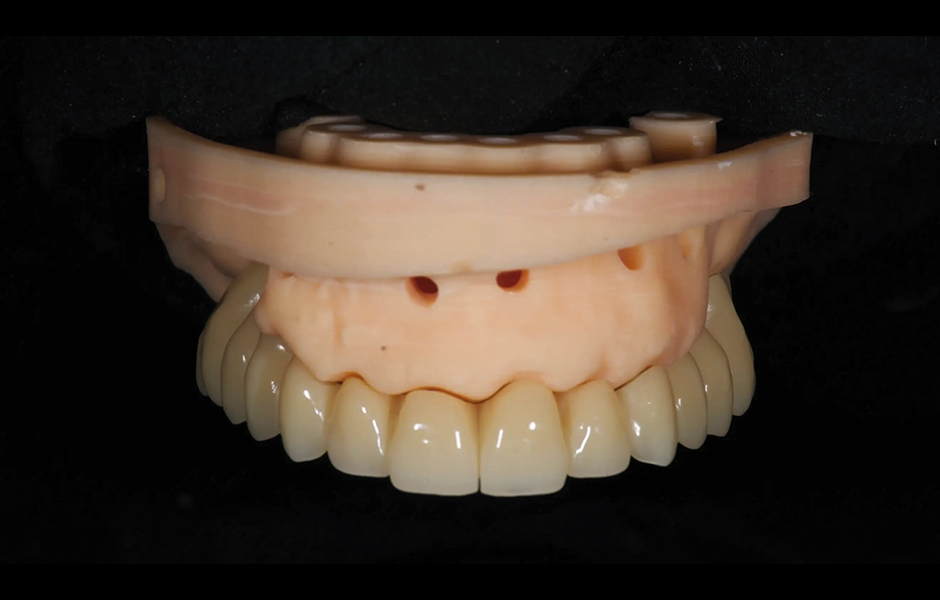

Při první návštěvě byly digitální otisky pořízeny pomocí skeneru Medit i700 k dokumentaci reziduálních zubů, měkkých tkání, stávající protetiky a protilehlého oblouku. Okluzní záznamy byly získány v aktuální vertikální dimenzi okluze a v centrální relaci. Pohyby mandibuly byly zaznamenány pomocí systému pro registraci čelistí zebris JMA (zebris Medical). Byly pořízeny intra- a extraorální fotografie. Na základě těchto dat byl vytvořen virtuální diagnostický wax-up a digitální simulace úsměvu (Smile Creator, exocad). Následně bylo naplánováno osm implantátů (obr. 3 a 4) podle nového wax-upu (exoplan 3.1, exocad) a předem byla vyrobena chirurgická šablona i dočasná kovem vyztužená protetika (obr. 5–7).

Obr. 5: Předem zhotovená provizorní protetická práce z PMMA.